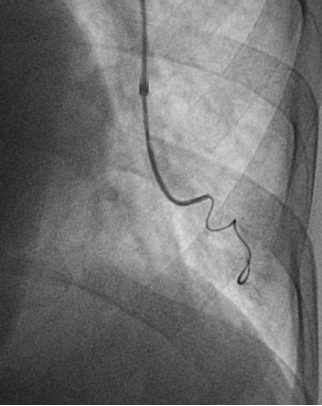

Maleux et al. J Cardiovasc Surg 2016

肺动静脉畸形栓塞